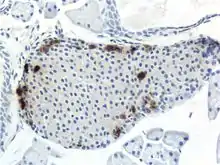

A pancreatic islet, stained.